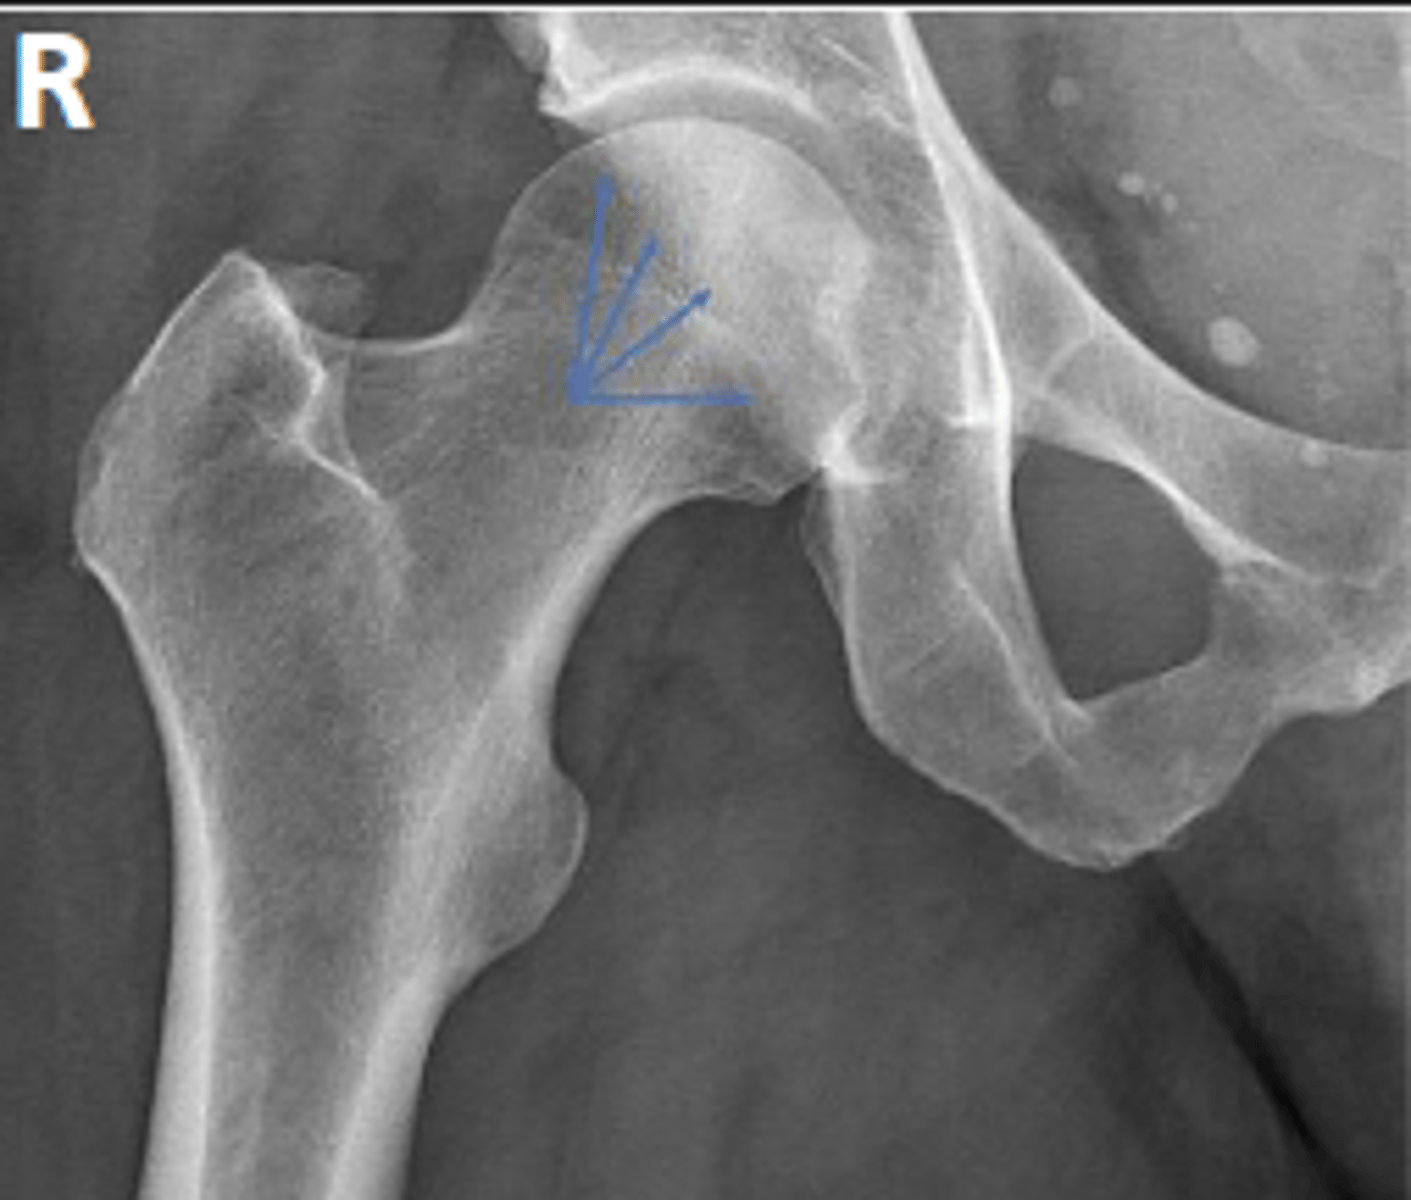

Posterior rim of the right acetabulum

What are the arrows pointing to?

Anterior rim of the right acetabulum

Intertrochanteric line of the right femur